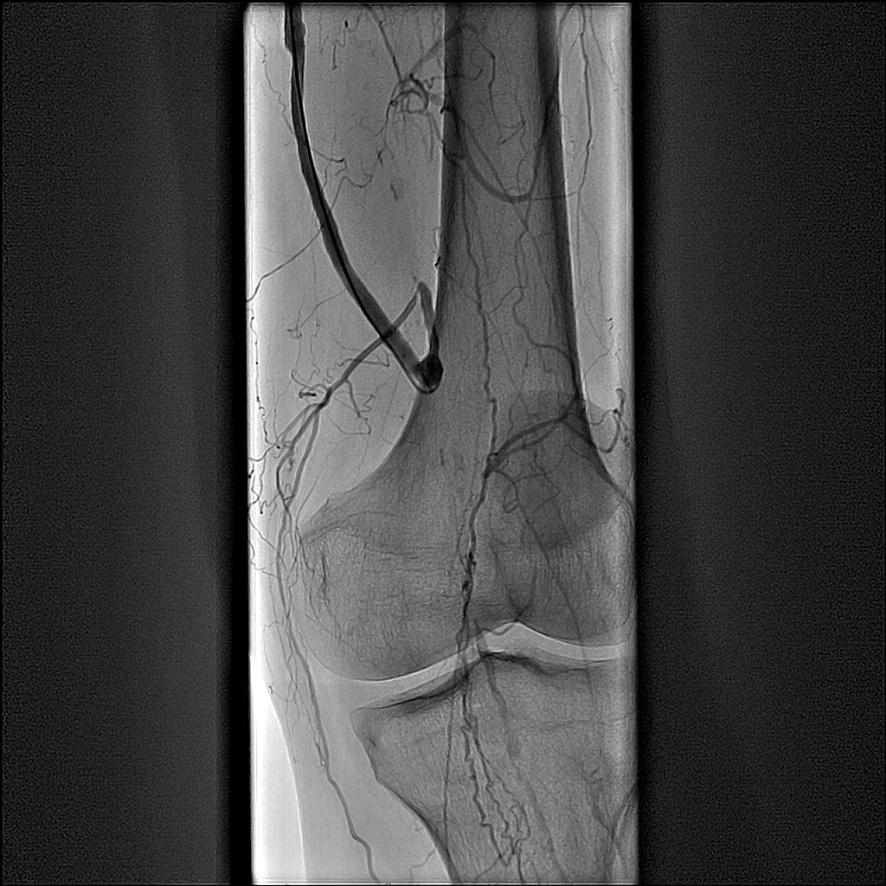

На ангиографии обнаружена окклюзия (непроходимость) левой подколенной артерии в месте дистального анастомоза бедренно-подколенного шунта (рис.1). Была выполнена реканализация и баллонная ангиопластика подколенной артерии с хорошим эффектом, однако пройти из подколенной артерии в артерии голени не удалось, вследствие окклюзии устьев передней и задней большеберцовых артерий (рис.2). За местом окклюзии артерии голени заполнялись по коллатералям (ветвям сосудов, обеспечивающим кровоснабжение помимо основного сосуда). Было принято решение о повторной попытке реканализации передней большеберцовой артерии.

![]() Рис.1 Окклюзия левой подколенной артерии |

![]() Рис.2 Реканализация и баллонная ангиопластика подколенной артерии; сохраняется окклюзия устья передней большеберцовой и задней большеберцовой артерий |